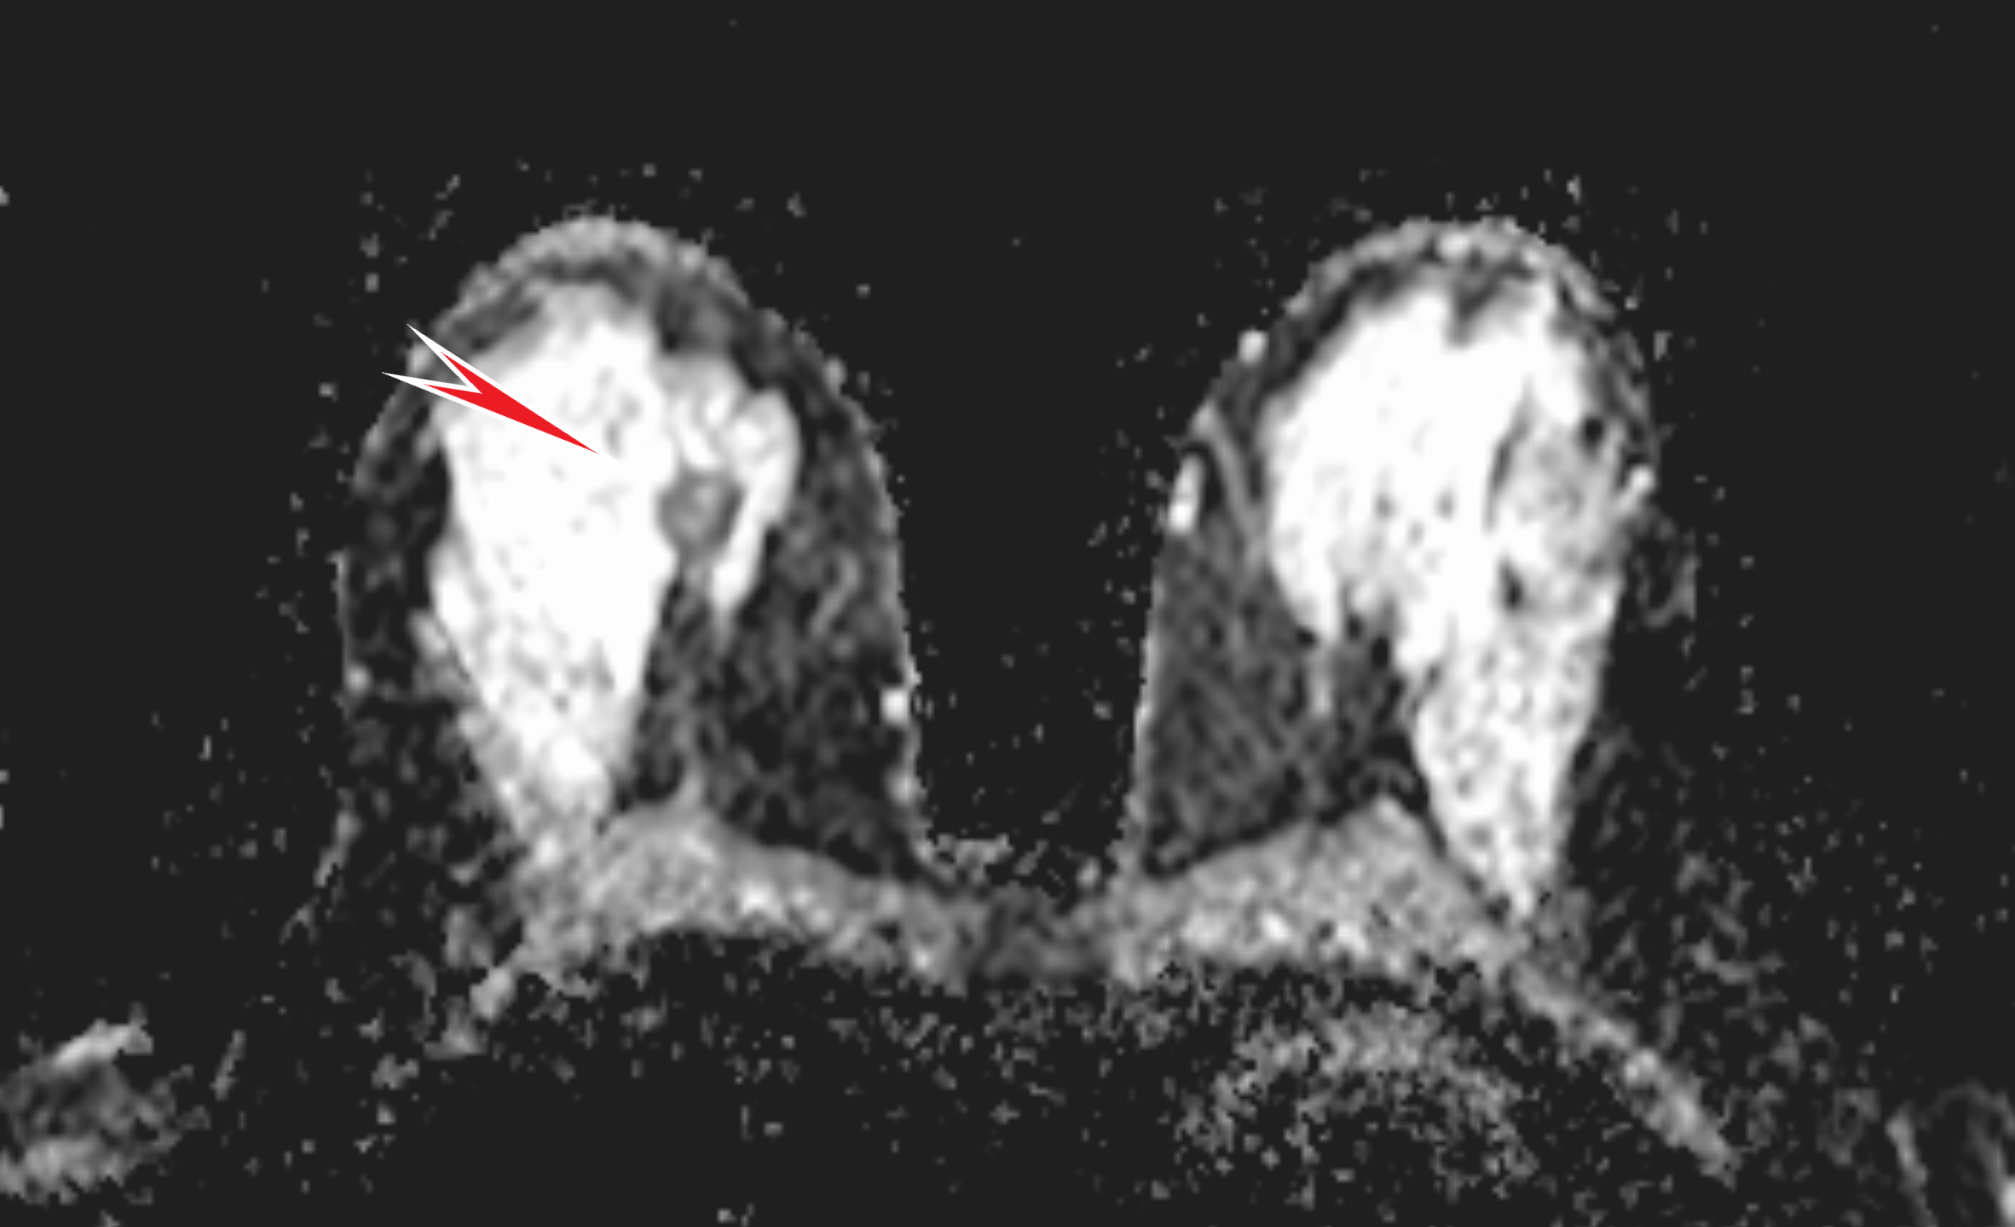

Дополнительно спустя несколько дней провели МРТ молочных желёз для исключения "мультицентричности" (т.е. для исключения других возможных очагов, не видимых на маммографии и УЗИ), где образование выделялось локальным снижением диффузии (увеличение числа клеток или размера клеток вызывает уменьшение внеклеточного пространства, в котором циркулирует жидкость, что видно на специальных секвенциях):